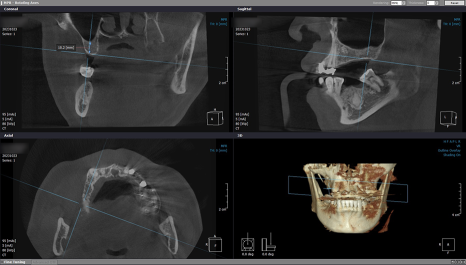

4개월의 골 유착 기간을 갖고

내원해 주신 환자분의

#14번 치아는 본을 뜨고 보철물 수복을 해드렸으며

2차 수술을 진행한 #16, #17, #46, #47번은

잇몸을 열고 커버 스크류 제거 후

힐링 어버트먼트를 체결해 드렸답니다.

2개월이 더 지나고 나서

잇몸이 둥글게 완성되어

다른 곳과 동일한 방식으로 코핑 연결 후

모양을 본뜨고 기공소에 의뢰했습니다.